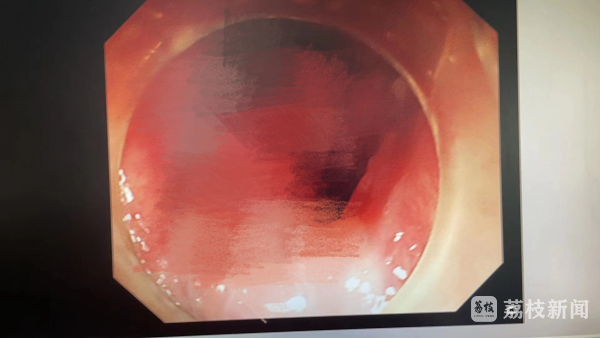

医生告诉她们,根据肿瘤的形状判断,这大概率是一个良性肿瘤。但是它特别“罕见”。一是肿块大,9CMX1CM的肿瘤堵塞了食管管腔的一半;二是基底部宽,长在食管入口,肿瘤蒂部与气管及咽喉部紧紧相连,手术剥离相当困难;三是血供丰富。肿瘤根部可见绿色血管网,丰富的血供滋养了肿瘤快速长大,但手术时极易大出血。

这个肿块呈半悬浮状态,如漂浮的水草。平常下垂在食管腔内,造成患者进食受阻、打嗝;偶尔在受到压力冲击(如打嗝、呛咳)或瞬间明显体位变化时,才会被顶到口腔内,所以很难被发现。医生说,这么大的肿块需要立即手术,否则随着体位的变动,肿瘤一旦压在声带上堵住气管入口,随时会引起窒息;肿瘤再长大堵塞食管腔,病人进食会越来越困难。

内镜下剥离(ESD)是最好的选择。但是肿瘤基底部太宽,术中手术深度极难把握。剥离浅了,可能会有肿瘤残留容易复发;剥离太深,又会伤及周围器官。最重要的是,肿瘤蒂部丰富的血供,剥离时必须要伤及血管。血喷出来会迅速遮住内镜,医生视野内红色一片看不到任何器官,很难着手止血;血液一旦喷到紧连着的气管入口,会迅速造成呛咳甚至窒息死亡。

手术比预想的顺利,林洁主任稳稳地在“针尖上绣花”,隔着一米多的软管,内镜顶端犹如长了“眼睛”,巧妙地避开食管、气管和咽喉,紧紧贴着肿瘤壁切开;剥离肿瘤基底部时,不出所料瞬间大量血喷了出来,与此同时,抢在内镜视野模糊之前,林主任已经“精准狠”地止住了血。半个小时左右的时间,顺利地将肿瘤“连锅端”了。